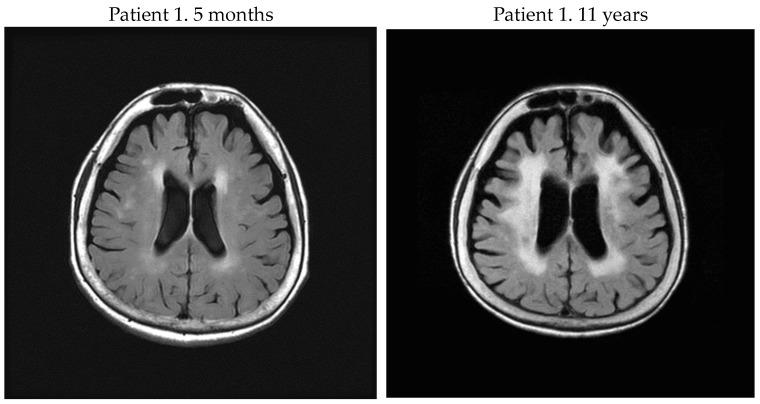

Human T-cell leukemia virus type 1-associated myelopathy/tropical spastic paraparesis (HAM/TSP) patients may have brain white matter (WM) lesions, but the association of these lesions with disease activity is poorly understood. We retrospectively evaluated the brain WM lesions of 22 HAM/TSP patients (male 4: female 18) including 5 rapid progressors, 16 slow progressors, and 1 very slow progressor. The severity of WM brain lesions on axial Fluid Attenuated Inversion Recovery images was evaluated utilizing the Fazekas scale, cerebrospinal fluid biomarkers, and proviral load in peripheral blood mononuclear cells. Imaging and biological data were compared at the first visit and a subsequent visit more than 4 years later. Patients with comorbidities including adult T-cell leukemia-lymphoma and cerebrovascular disease were excluded. The results revealed that brain WM lesions in the rapid progressors group were more pronounced than those in slow progressors. In patients with HAM/TSP, severe and persistent inflammation of the spinal cord may cause brain WM lesions.